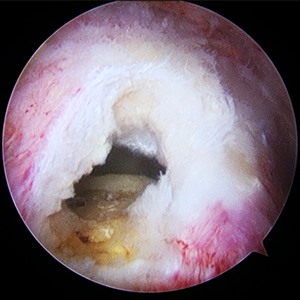

整形外科における手術の役割 肩腱板断裂治療のアルゴリズム 不全断裂 小断裂 中~大断裂 一次修復不能広汎性断裂 保存療法(リハビリ:運動療法/物理療法) 手術療法 関節鏡下腱板修復術 腱移行術、腱移植術、リバース型人工関節 腱板断裂の治療の基本は保存療法ですが、それが反応しない場合には、関節鏡下腱板修復術が適応されます。 修復前 修復後 関節鏡下腱板修復術は「肩に小さな穴を数か所開け、関節鏡で中をのぞきながら縫い合わせる方法」で、私の得意分野です。 不全断裂 小断裂 中~大断裂 一次修復不能広汎性断裂 保存療法(リハビリ:運動療法/物理療法) 手術療法 関節鏡下腱板修復術 腱移行術、腱移植術、リバース型人工関節 縫いきれないほどの大きな断裂には、腱の移植や人工関節が必要になります。 手術を望まない方へは、間葉系幹細胞を用いた再生医療の提供に取り組んでいます。